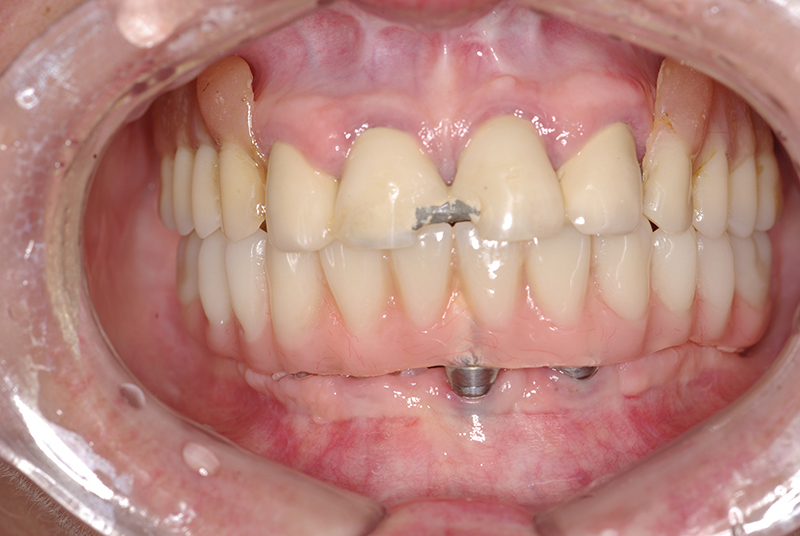

A Carga Imediata é uma técnica odontológica avançada que permite a colocação de uma prótese dentária fixa logo após a cirurgia de instalação dos implantes ou em poucos dias. Isso elimina a espera tradicional de meses para a integração completa do implante ao osso, oferecendo uma solução rápida e segura para restaurar dentes perdidos.

- Fixação da Prótese: Em até 72 horas após a cirurgia, a prótese provisória é instalada, permitindo que o paciente recupere a funcionalidade e a estética imediatamente.